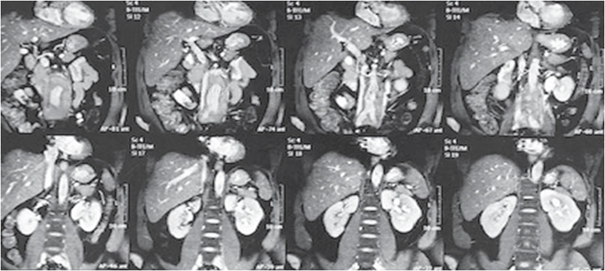

Paciente masculino de 50 años de edad con antecedente patológico de urolitiasis desde hace 25 años, consultó por primera vez a urgencias en el 2016 por cuadro de dolor abdominal irradiado a región lumbar, por lo que realizaron tomografía de abdomen simple que evidenció litiasis renal bilateral, litiasis ureteral proximal izquierda condicionando ligera uretero hidronefrosis izquierda y adicionalmente componente de tejido blando interaortocava y periaórtico asociado a conglomerado ganglionar de naturaleza neoplásica linfoproliferativa, razón por la que se decidió la toma de TC de abdomen con contraste, que evidenció conglomerados de adenopatías retroperitoneales, con pared aortica sin dilatación aneurismática con lesión fusiforme de bordes bien definidos con densidad homogénea de tejidos blandos que rodea la aorta y la cava. Para caracterizar mejor los hallazgos tomográficos, se realizó resonancia de abdomen con contraste que se muestra en la figura 1.

Masa de hasta 20 mm de espesor que envuelve la aorta abdominal en su porción infrarrenal hasta la división aortoilíaca, produciendo ligero desplazamiento de la vena cava inferior y presentado señal intermedia en T1 y T2, la aorta abdominal infrarrenal presenta ectasia de hasta 28 mm de diámetro.